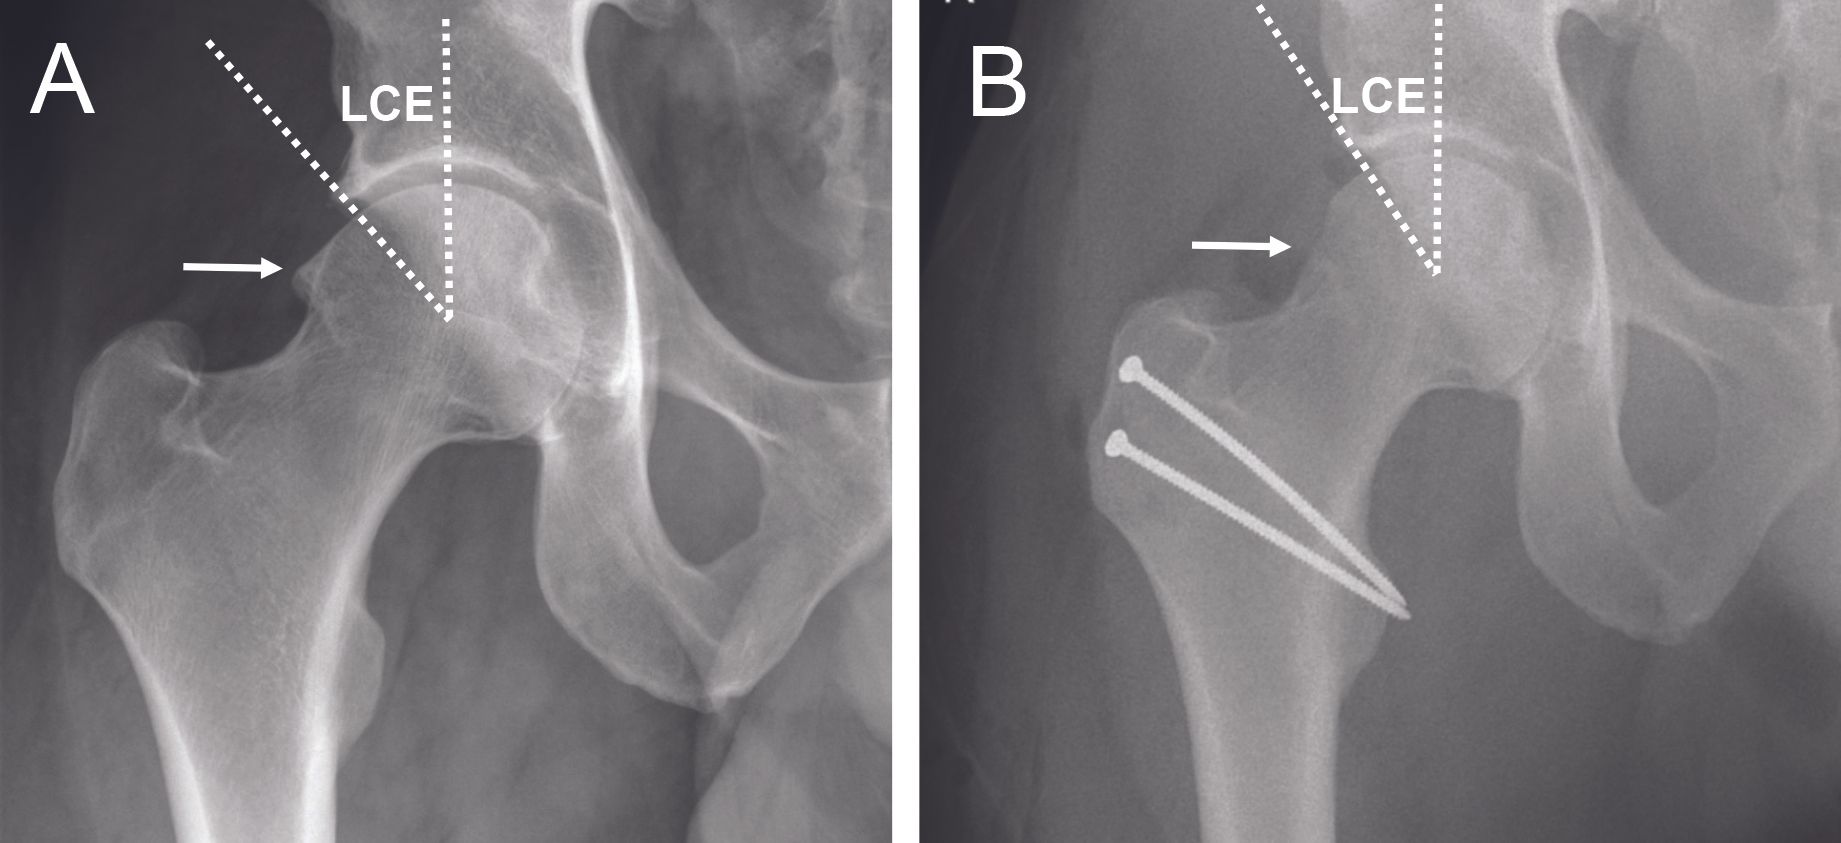

Excessive coverage of the acetabulum can lead to a pincer-type FAI. This is seen with a Wiberg Lateral Center Edge (LCE) angle greater than 33° (4) (Figure 2). Pincer-type FAI may also occur in cases of acetabular protrusion (Figure 3) when the femoral head is medial to the ilio-ischial line.

The periacetabular osteotomy (PAO) was initially described to treat dysplasia, and then the anteversion periacetabular osteotomy (19) was described to treat retroversion of the acetabulum that can lead to FAI (Figure 14).

The surgery is performed using a modified anterior Smith-Petersen approach. The principle is based on several osteotomy cuts, at the level of the ischium, the superior branch of the pubis, the supra-acetabular region and the retroacetabular region, while keeping the posterior column in continuity. Mobilization of the fragment comprising the acetabulum allows reorientation and thus correction of the version of the acetabulum. This fragment is then stabilized with screws.

This is a more extensive surgery, reserved for young patients under 40 years of age (20) in cases of global retroversion of the acetabulum with a retroversion >30% (Figure 15).